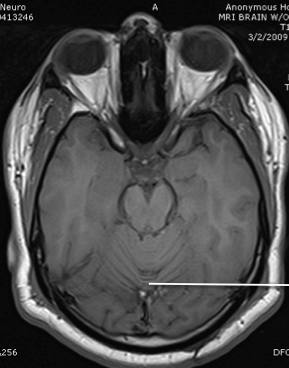

amygdala

hypothalamus

hippocampus

tegmentum and tectum of midbrain

third ventricle